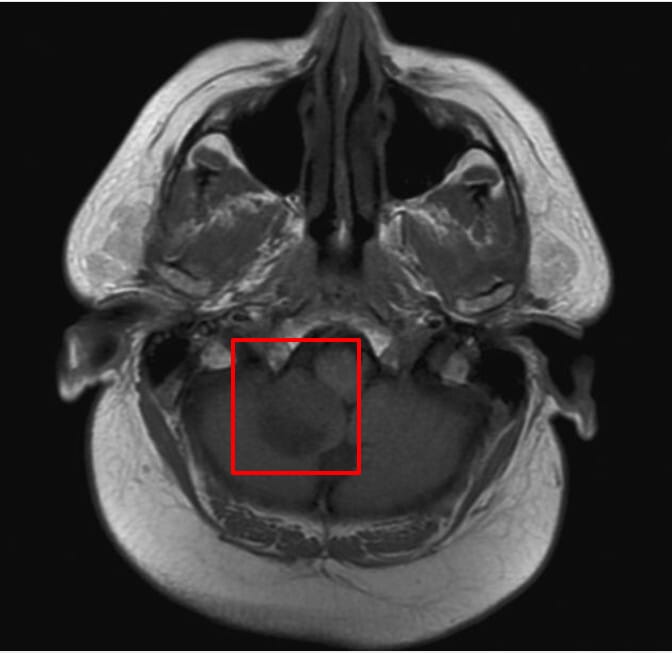

뇌 MRI 소견

소세포폐암은 뇌 전이가 흔합니다. 뇌 전이 병변 영상 소견을 정리해보겠습니다.

| 다발성 조영 증강 병변 |

| 회백질 경계(gray-white junction)에 전형적인 뇌 전이 병변이 관찰됨 |

| 무증상 뇌 전이 |

| 초기에는 무증상이나 영상에서만 확인되는 경우 많아 예방적 방사선 치료 고려 |

Gaillard F, Cerebellar metastasis – small cell lung cancer. Case study, Radiopaedia.org (Accessed on 20 Apr 2025) https://doi.org/10.53347/rID-10248